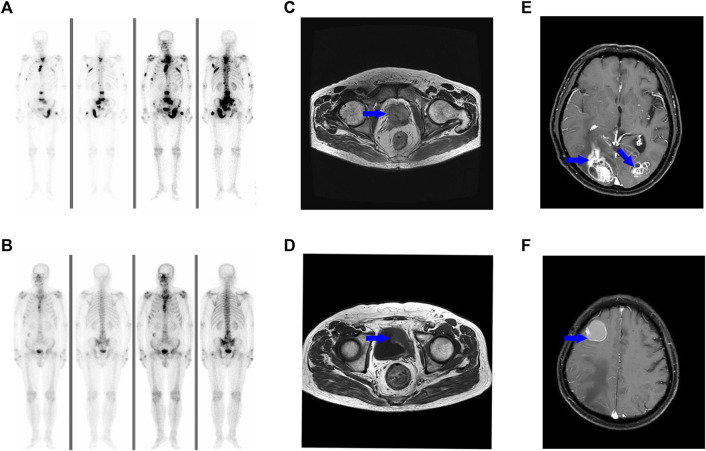

Squamous differentiation of prostate cancer, which accounts for less than 1% of all cases, is typically associated with androgen deprivation treatment (ADT) or radiotherapy. This entity is aggressive and exhibits poor prognosis due to limited response to traditional treatment. However, the underlying molecular mechanisms and etiology are not fully understood. Previous findings suggest that squamous cell differentiation may potentially arise from prostate adenocarcinoma (AC), but further validation is required to confirm this hypothesis. This paper presents a case of advanced prostate cancer with a combined histologic pattern, including keratinizing SCC and AC. The study utilized whole-exome sequencing (WES) data to analyze both subtypes and identified a significant overlap in driver gene mutations between them. This suggests that the two components shared a common origin of clones. These findings emphasize the importance of personalized clinical management for prostate SCC, and specific molecular findings can help optimize treatment strategies.